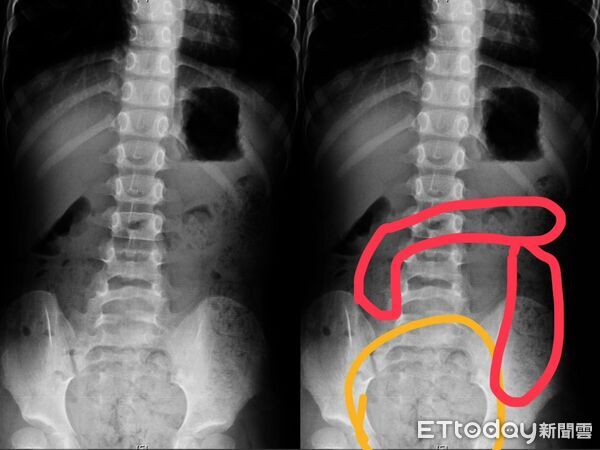

▲女童剛上小學憋便意,腹部脹大積屎被送到急診。(圖/記者許宥孺翻攝)

另一例則是一名6歲女童,因肚子痛得直哭叫,腹部明顯異常脹大,被家長送到急診後,經腹部X光檢查,發現她一肚子大便。媽媽表示,女兒可能剛上小學,還沒習慣上課節奏,有便意也忍著不去廁所,就連幾天沒上大號也記不清,直到症狀嚴重掛急診。